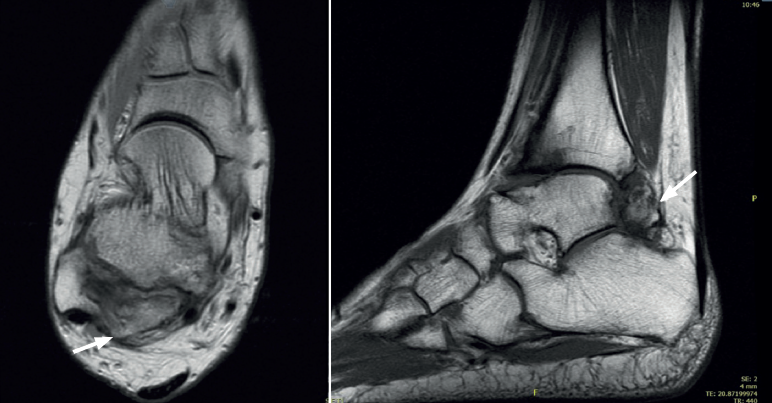

Es una entidad rara de etiología desconocida que afectaría a 1 de cada millón de personas, es 3 veces más frecuente en el varón y presenta el aspecto clínico e histológico de un osteocondroma que asienta en la epífisis en vez de la zona metafisaria del hueso en crecimiento(24,25)(Figuras 4 y 5).

En adultos (Figuras 6 y 7), se cita como causa de pinzamiento doloroso en la cámara posterior del tobillo(50), aunque también como causa de impingement anterior(51), o confundirse con un osteocondroma a pesar de sus diferencias histológicas. Mientras el osteocondroma reproduce una arquitectura similar a la de la placa de crecimiento, la displasia epifisaria hemimélica muestra en su cubierta cartilaginosa áreas con acúmulos de condrocitos y pequeñas áreas de cartílago calcificado no reabsorbido(52). Por otra parte, la presencia de osteocondromas en la parte posterior del astrágalo es muy rara. En una serie de 7 casos en los que se produjo rotura a través del pedículo en relación con ejercicio físico, Carpintero et al. no señalan ninguna en esta localización(53).